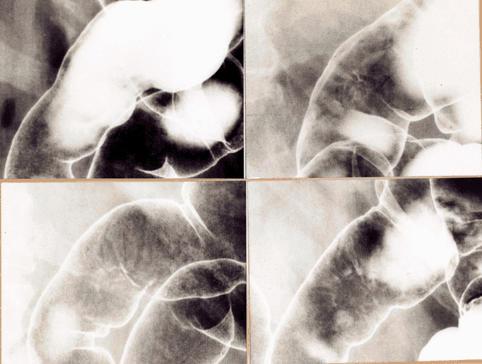

Cáncer avanzado de Colon de tipo ulceración infiltrada que mostró formación similar al tipo superficie deprimida (tipo IIc), acompañado de convergencia de pliegues

Tokyo Pref., Centro Nacional de curaciones de Cáncer, Hospital Central y Centro Kyusyu de Curaciones de Cáncerc

Tumor Epitelial Maligno/Adenocarcinoma

colon/transverso

Rayos X

Tipo 3(Tipo ulcerado de bordes infiltrados)/

25 - 29

mp